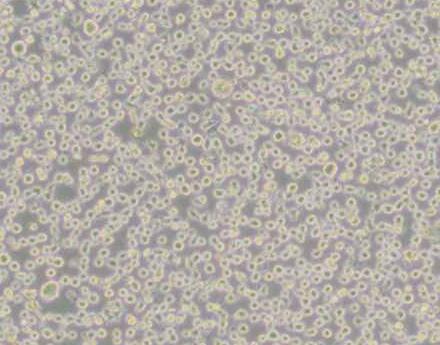

细胞形态:

淋巴母细胞样

细胞形态 淋巴母细胞样

生长特性 悬浮细胞

悬浮细胞